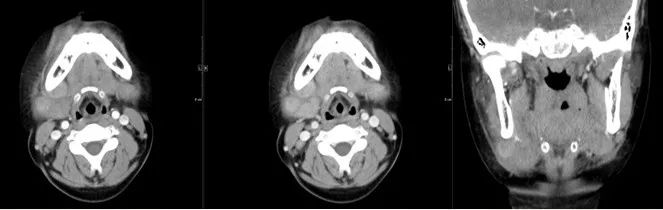

04 咀嚼肌间隙、颌下间隙、左侧颞下间隙,颊间隙,翼颌间隙

男,55岁,左下后牙反复肿疼1年余,加重1月余,疼痛剧烈伴张口受限,面部肿胀。

咀嚼肌间隙有脓肿形成。